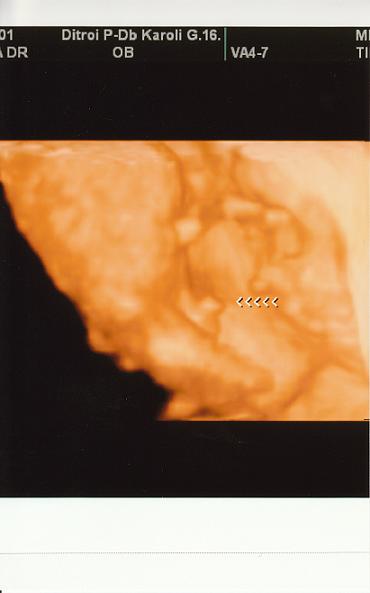

Ma voltunk a genetikai uh-n es 3d-n. Minden rendben talaltatott, mindene megvan, noha nehez volt vegig kovetni, mert nagyon ficankolt. Az uh-s neni azt mondta, vegyek sok sportcipot! :lol:

Vegre rajottem, hogy lehet kepet felrakni, ugyhogy ime a fotok:

Azt hiszem, nem kell magyarazni, ezen a kepen mi lathato:

Kép